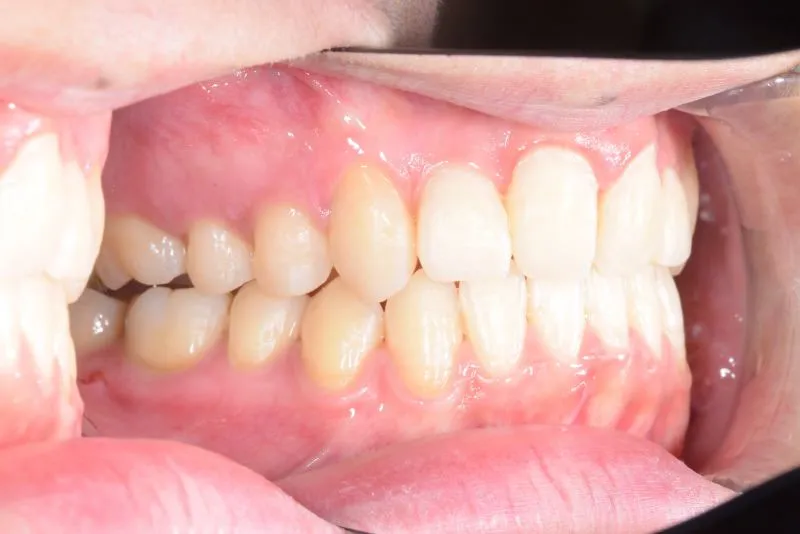

• 治療終了後

治療終了後

治療回数42回、3年1ヶ月の治療期間で矯正治療を終了しました。

主訴が改善され、ご満足頂きました。